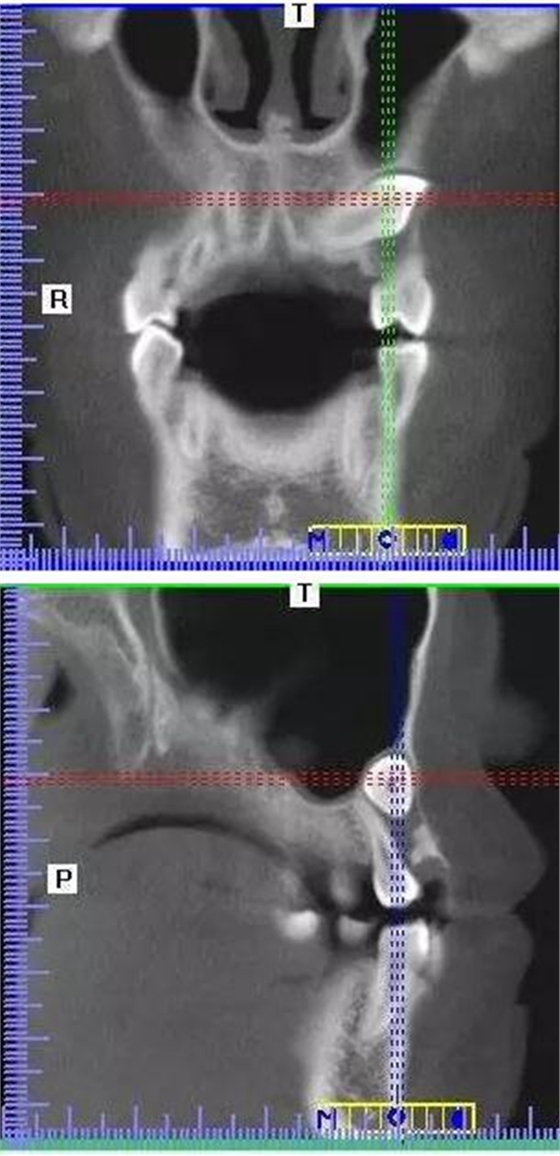

本案:患兒,女,14歲,因牙齒矯正來院,檢查見83滯留,43未見萌出,拍片發(fā)現(xiàn):43埋伏阻生于31、41、42根尖下方,按照正畸診療計劃,擬行43拔除術。

CBCT顯示